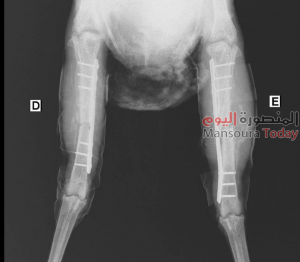

كان طبيب بيطري ادعى إجراء عملية جراحية عاجلة لإنقاذ دجاجة سقطت من فوق سطوح أحد المنازل المرتفعة بمدينة في مرسى علم بالبحر الأحمر، وتعرضت لكسر شديد في قدميها، ثم ثبت كذب الطبيب حيث تبين أن العملية لفرخة في البرازيل.